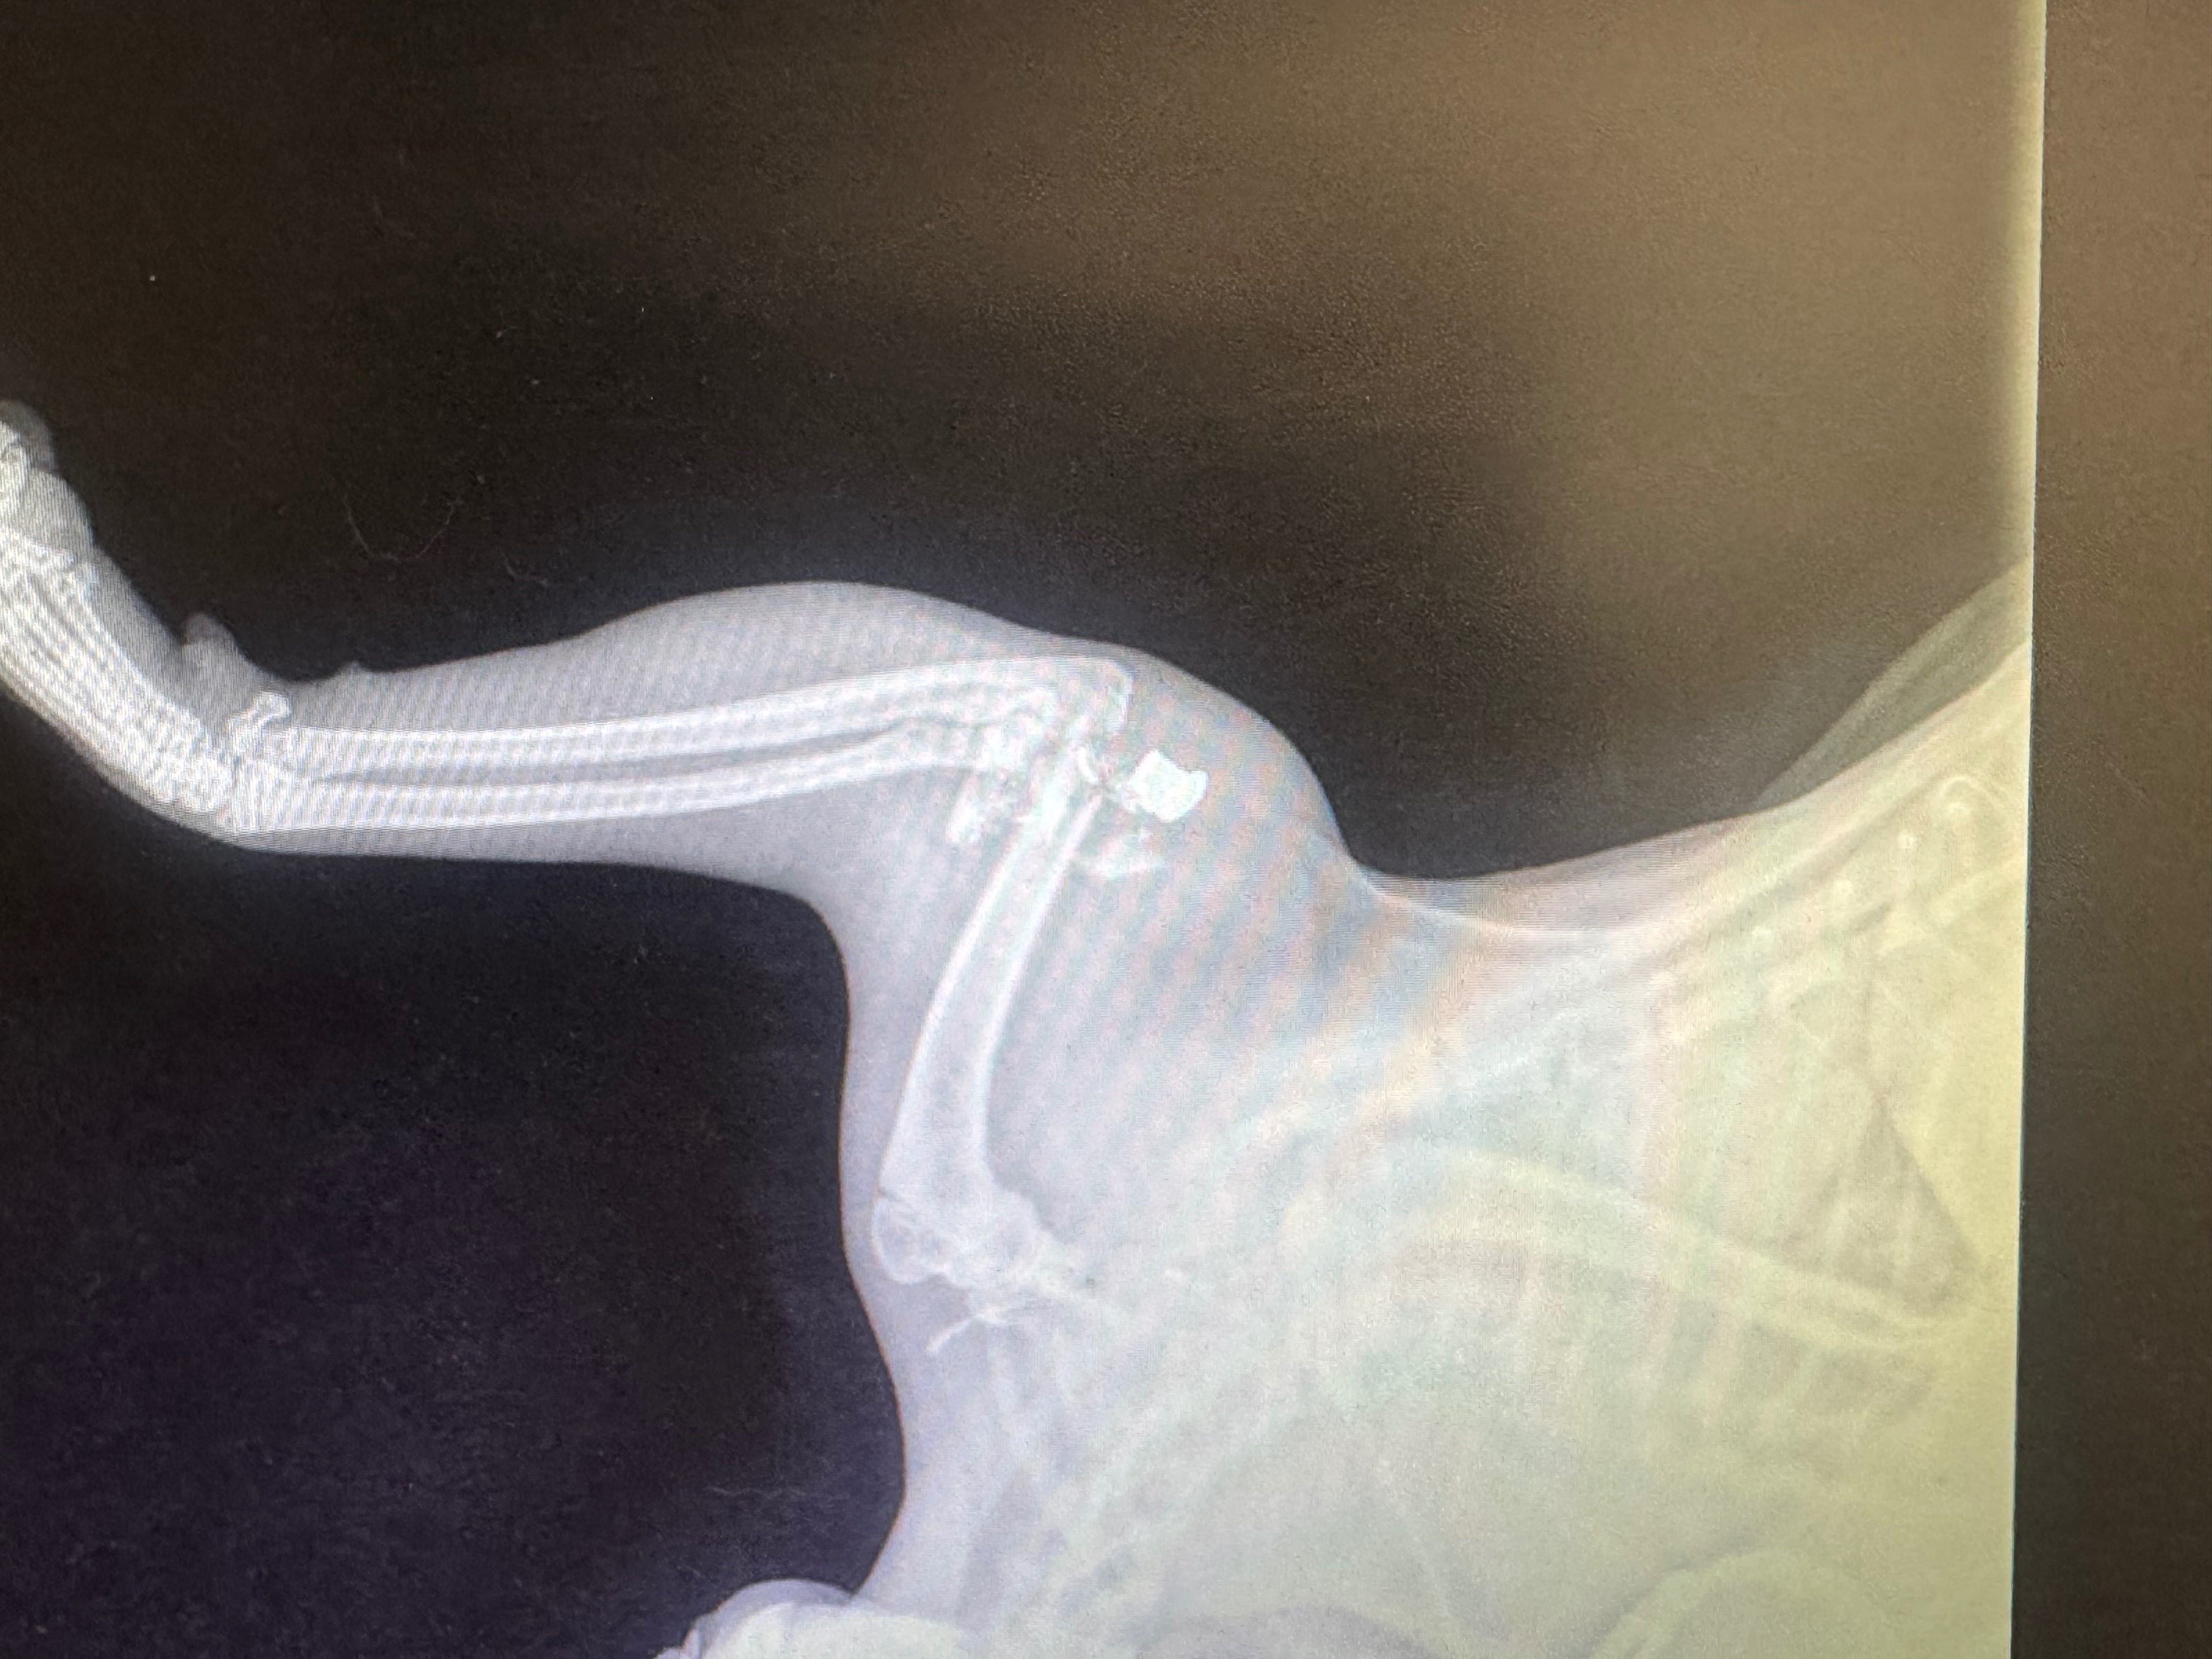

Hello, friends! My youngest brother’s cat, Beans, was very cruelly attacked by someone while he was venturing outside. My family found him outside unable to walk and discovered he was shot. He was rushed to the emergency veterinarian where they later determined the wound was far more severe and the leg that was injured will have to be amputated. Unfortunately, the bill is not easily affordable, and we are seeking the help of family, friends, and anyone kind enough to help donate towards the expenses. This cat means the world to my youngest brother, and my little brother is the sweetest soul on the planet. We appreciate any and all help donating and sharing this story.